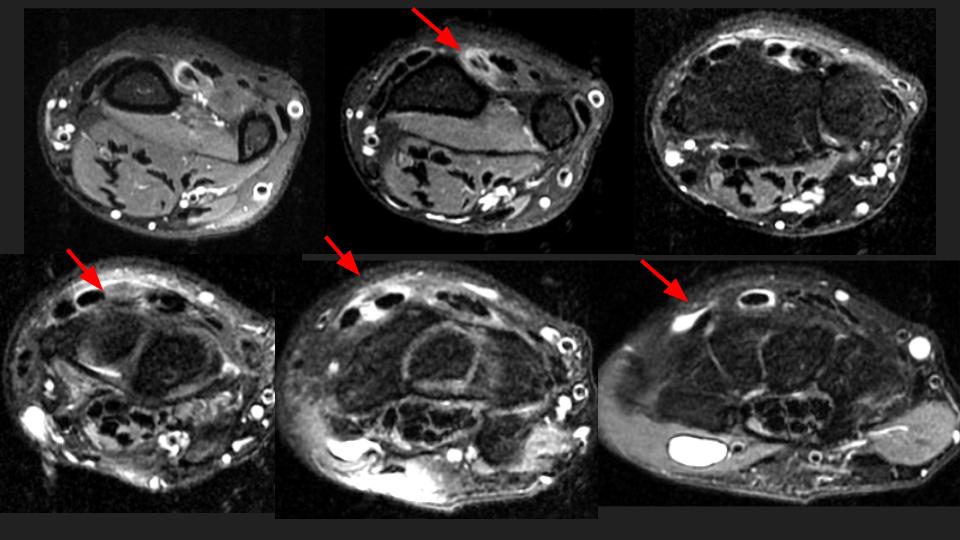

35M 5 months pain, referred to evaluate the scapholunate ligament

Red arrows point to the EPL which appears partially torn proximal to the level of Listers tubercle. On MRI (I wish this were US, I hear you) the distal remnant at the site of intersection with the 1st extensor compartment looks quite attenuated, but I see something passing over ECRL/ECRB with fluid signal between. Is this a complication of neglected proximal intersection syndrome? I have never seen it progress to EPL tear, but apparently there are Italian radiologists (see attached abstract) who have. Reference article.

extensor pollicis longus tendon ( RID2378 )